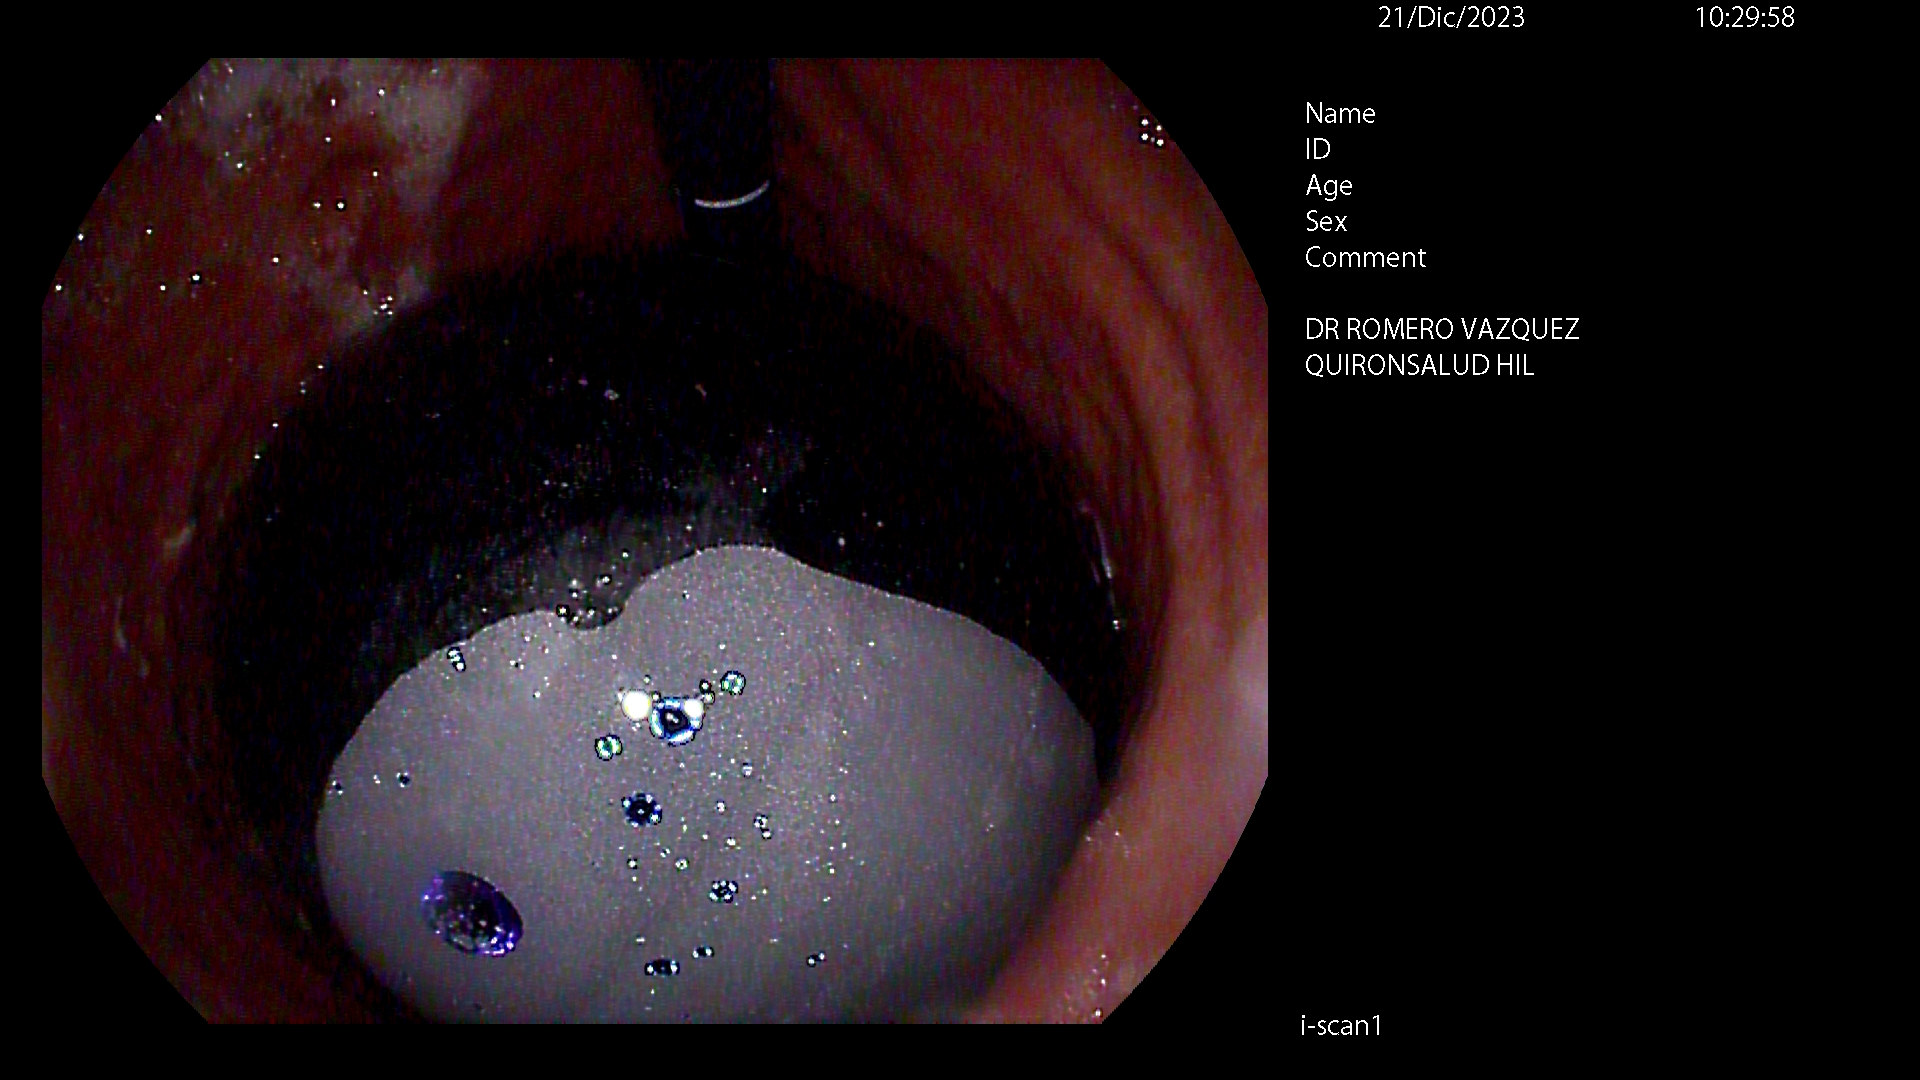

BALÓN INTRAGÁSTRICO

El balón intragástrico es un implante temporal de silicona, que rellenamos con suero, normalmente unos 500-600 cc, con un colorante (azul de metileno) para detectar cualquier posible anomalía futura (pérdida de contenido o rotura), una vez se aloja en el estómago y ocupa una parte importante del mismo. Esto genera dos mecanismos clave para aumentar la saciedad y por ello, perder peso:

Su colocación se realiza en la mayoría de las ocasiones por gastroscopia con sedación profunda administrada y controlada por anestesista, siendo una técnica ambulatoria (no precisa ingreso hospitalario) y su retirada, tras haber cumplido su función a los 6-12 meses, dependiendo de cada caso concreto, por gastroscopia con intubación y anestesista general, para minimizar los posibles inconveniente inherentes a la técnica, igualmente de forma ambulatoria.